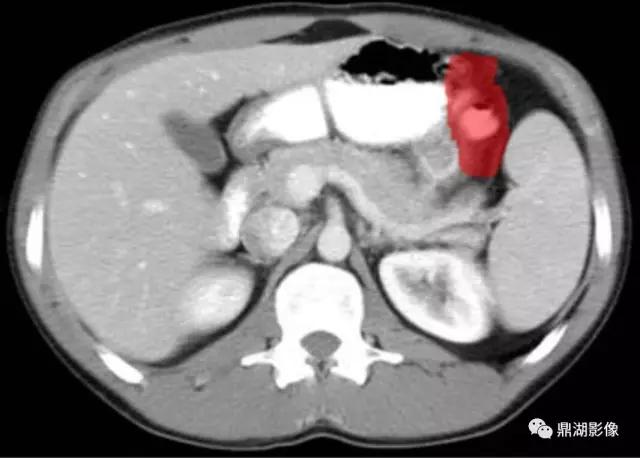

脾区(Splenic Flexure)

脾静脉(Splenic Vein)